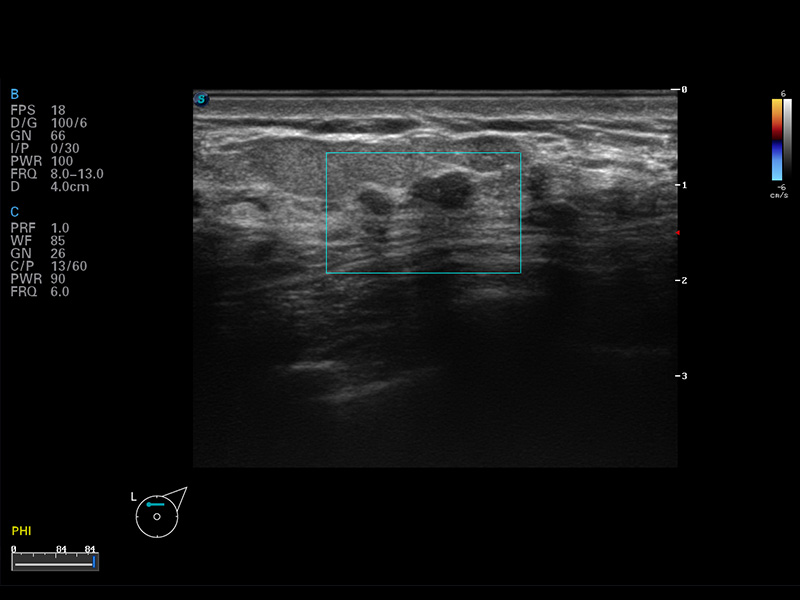

便携式彩色多普勒超声诊断仪

S8 EXP便携式彩色多普勒超声诊断仪是玖鼎集团研发的高端全身应用型便携彩超。高通道的VIS平台融合可视化(Visual)、智能化(Intelligent)和人性化(Smart)的特点,配以玖鼎集团自主研发生产的探头大家族,使您能够快速、准确的获得病人信息,提高工作效率的同时减轻疲劳。

谐波成像